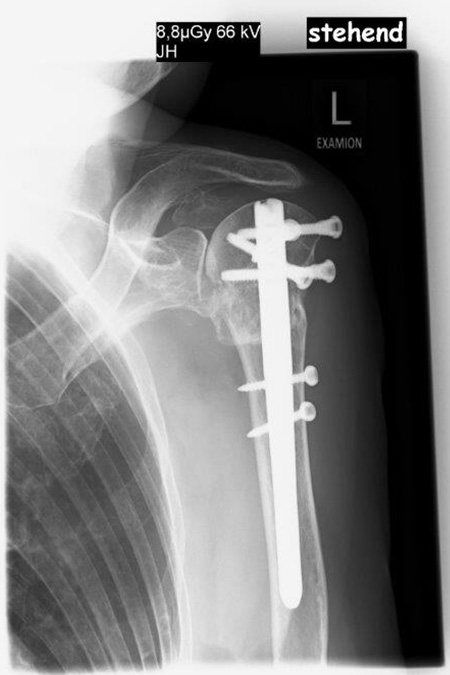

„Ich war gestürzt beim Fahrradfahren und der Bruch war mit einer Platte und Schrauben versorgt worden. Zunächst hatte ich kaum Probleme aber mit der Zeit bekam ich innerhalb des ersten 6 Monate Schmerzen und die Beweglichkeit wurde immer schlechter. Ich konnte meinen Arm fast gar nicht mehr anheben. Mein Hausarzt hat mir dann die Orthopädie an der Rosenhöhe empfohlen. Der Oberarmknochen war nicht mehr gut durchblutet und das Schultergelenk musste ersetzt werden. Jetzt komme ich im Alltag wieder ganz gut zurecht und übe noch fleißig. Die Schmerzen sind nicht mehr da.“

79 Jährige Patientin mit Oberarmkopffraktur und Plattenosteosynthese auswärtig versorgt stellt sich hier mit einem völligen Schultergelenksfunktionsverlust und Zusammenbruch des Oberarmknochens sowie Verschiebung bei liegender winkelstabiler Platte vor.

Es wurde die Platte entfernt und das Gelenk mit einer zementfreien Inversen Schultergelenksprothese nach Lösung der Verklebungen und Neufixierung der Sehnen wieder aufgebaut. 3,5 Monate nach operativer Versorgung sind die Sehnenansätze gut eingeheilt und eine ansprechende nahezu schmerzfreie Funktion erreicht.